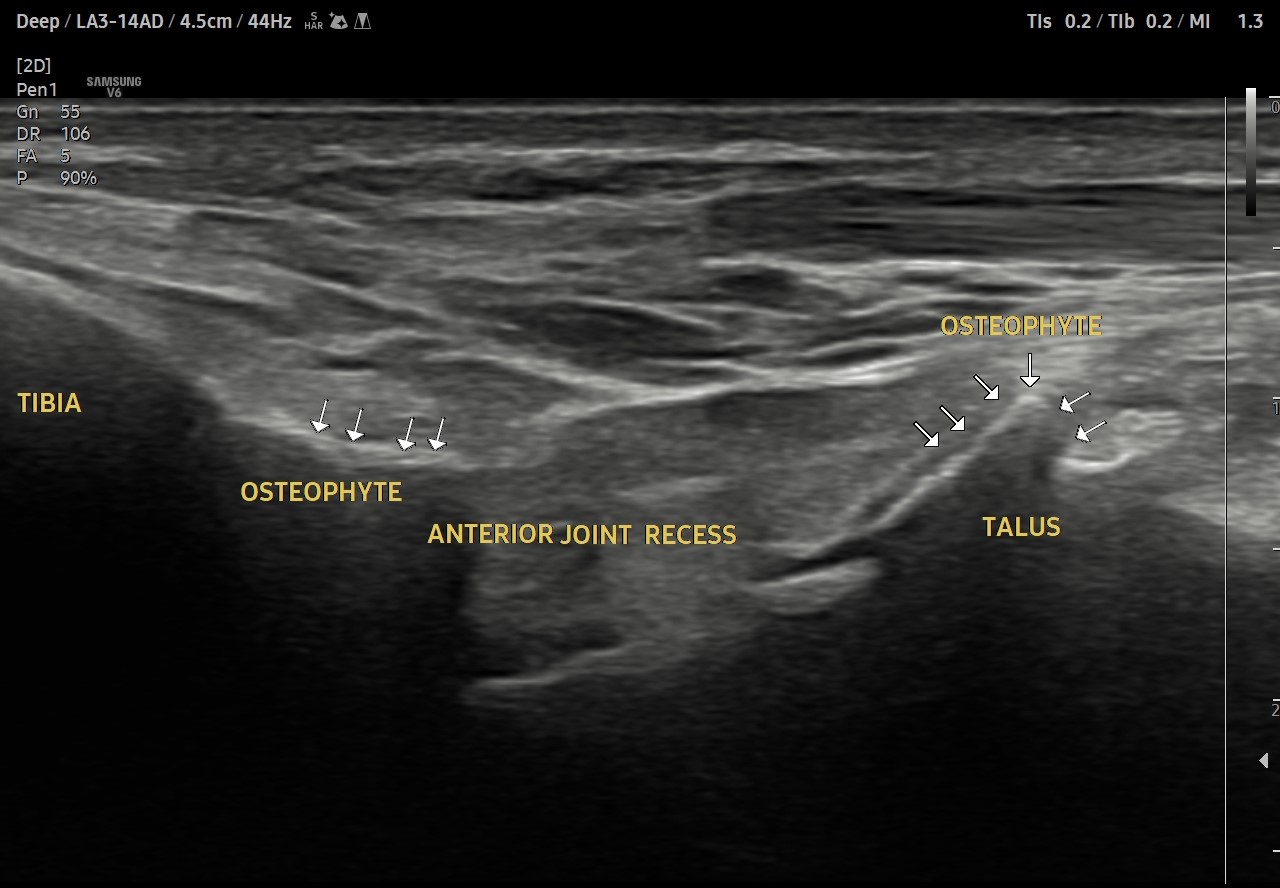

Anteromedial ankle impingement

Case of Anteromedial ankle impingement due to osteophytic growths at Tibia and head of Talus bone